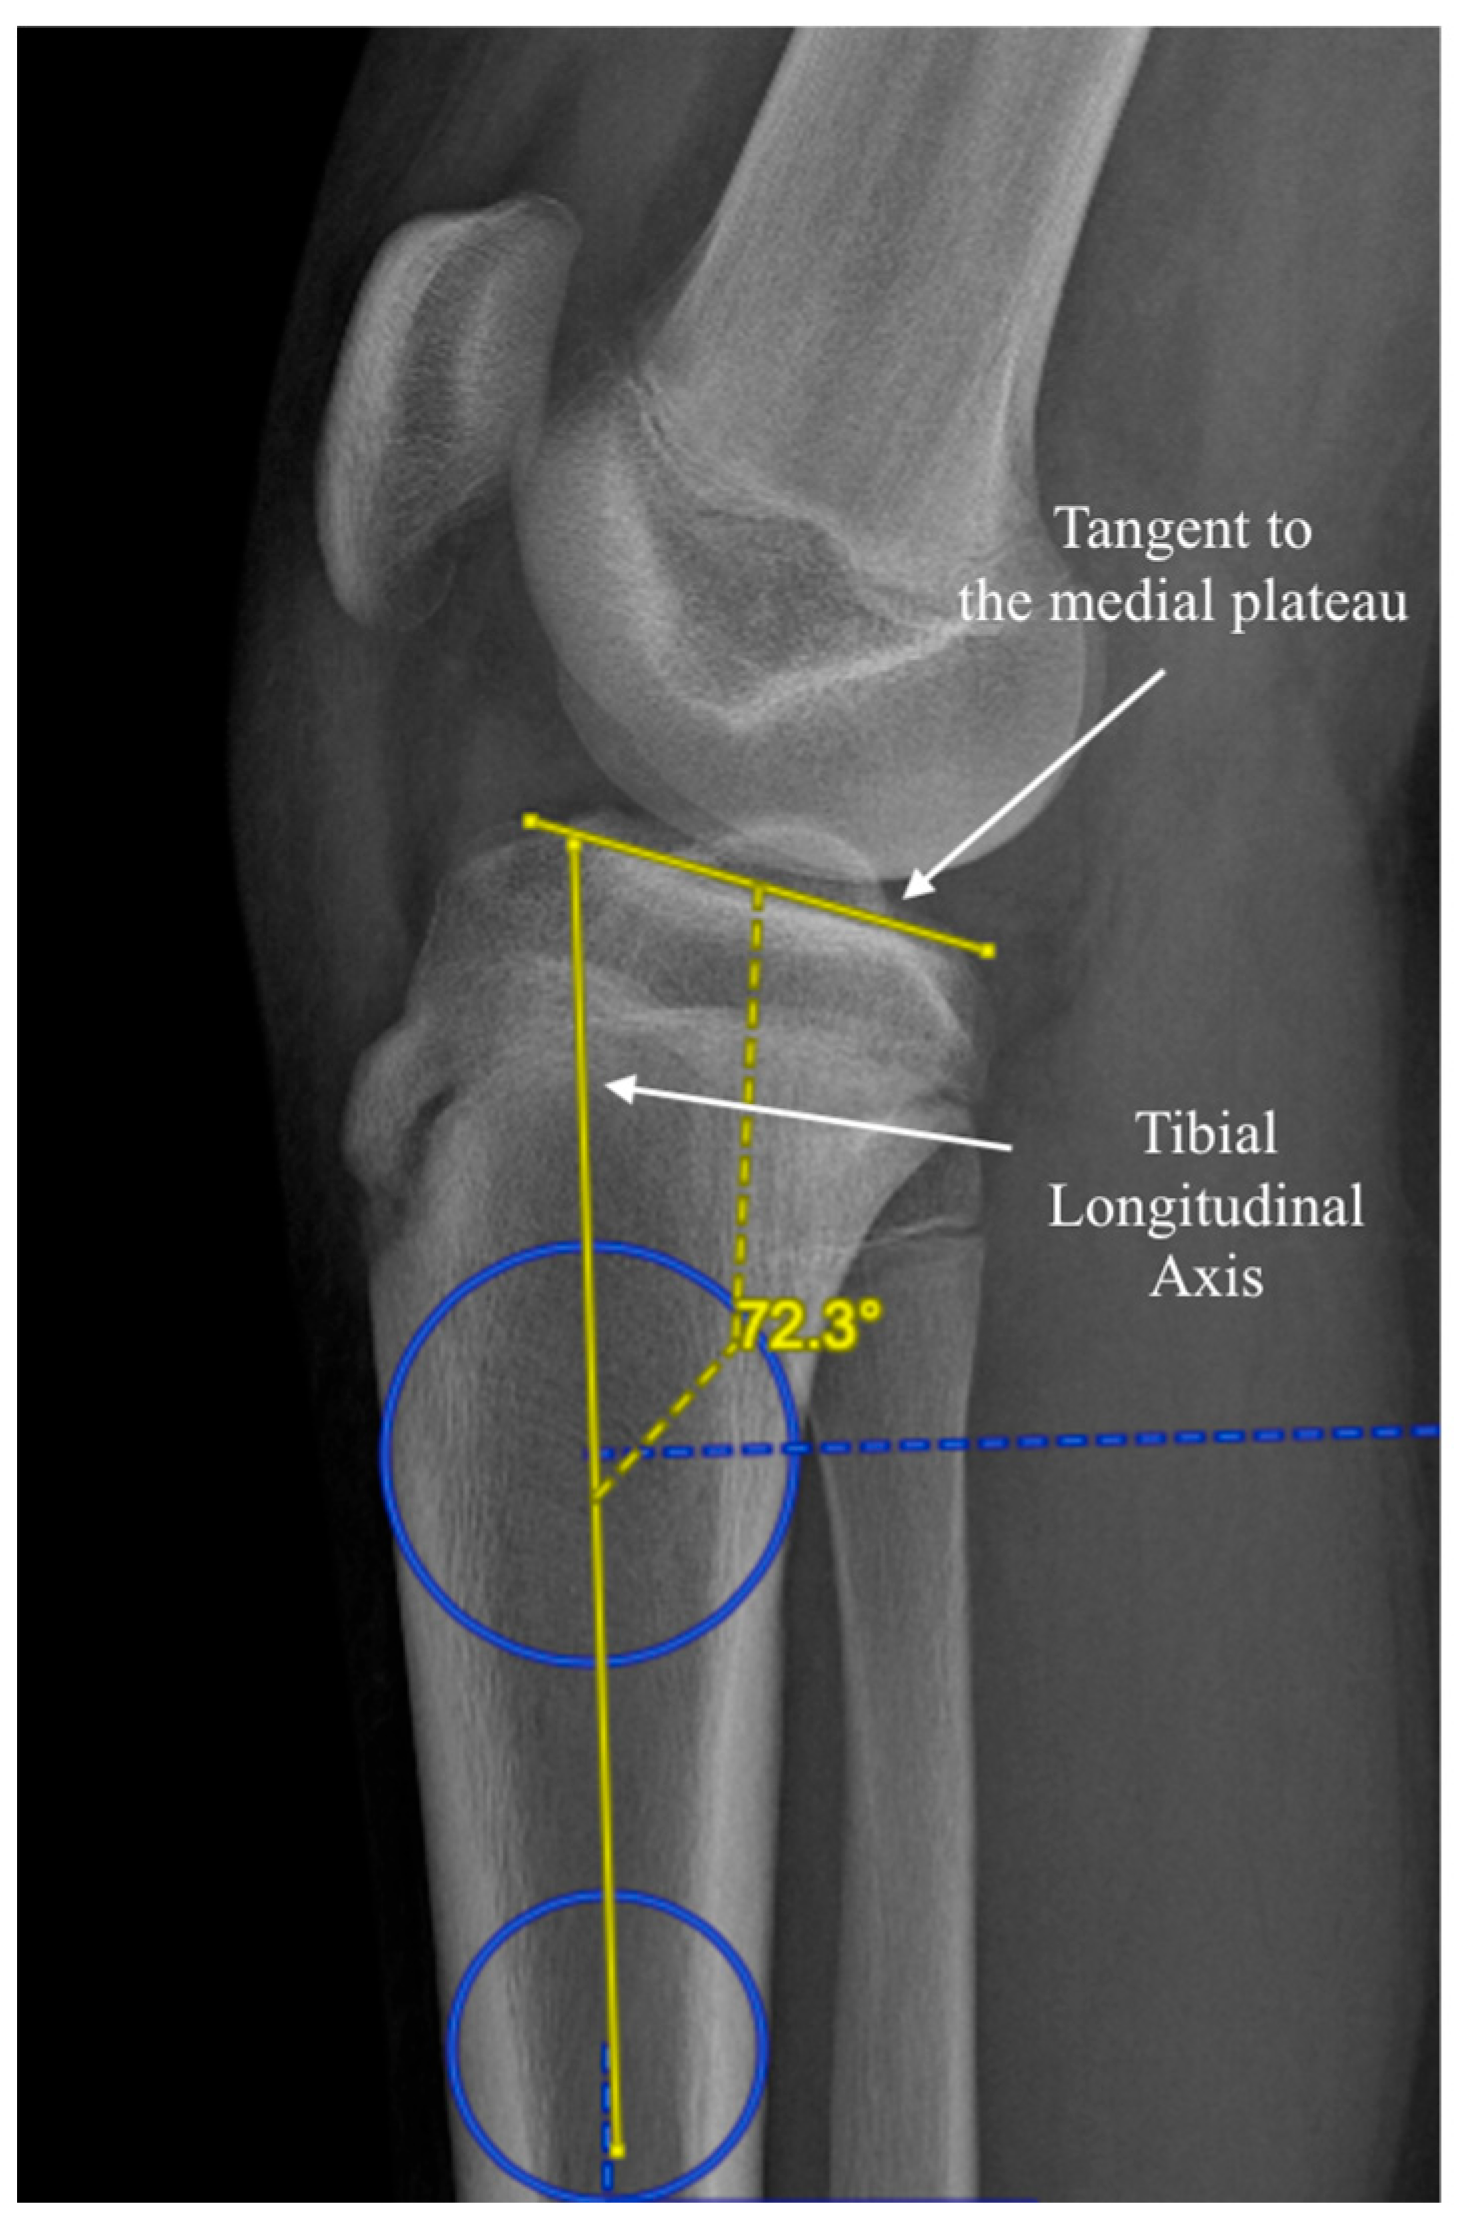

2.2. Measurement Methods